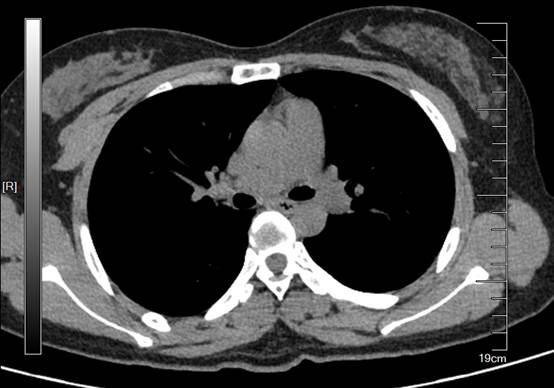

接诊的耳鼻喉科医生给小程开了胸部CT,显示食管中段腔内骑跨的高密度影,一端与后方的主动脉分界不清,遂告知患者转诊消化科。消化科医生接诊后,立即汇报蒋彩凤主任,蒋主任了解情况后高度重视,因为骨头一旦刺破主动脉,很快将出现大出血从而危及生命。为了精确评估骨头与血管关系,做了胸部增强CT后发现骨头与主动脉紧贴,幸运的是,主动脉内未见明显造影剂外渗。尽管如此,内镜下取出的难度仍然非常大,在松动异物和取出过程中食管蠕动,随时有二次损伤食管壁或者刺破主动脉的可能,为全力保证患者生命安全,当下即刻联系胸外科、麻醉科、中心ICU、急诊科前来会诊。

图1 术前CT下的鸭骨